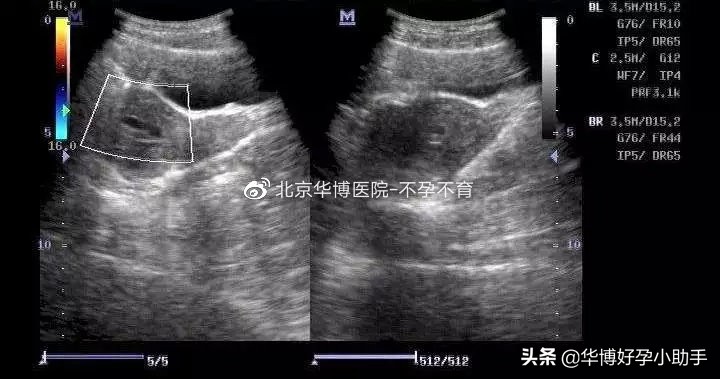

宫腔积液,顾名思义,就是子宫内出现了一些液体,通常是通过B超发现的。从B超上来看,宫腔内会有一个基本透亮的低回声区。